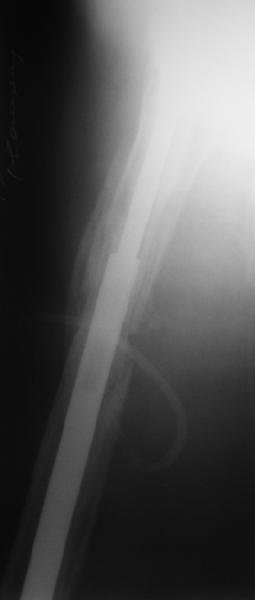

Female, rheumatoid, THA in 2003, car accident in 2006, failed plating. Nailing in Oct 2007. The nail is solid with hollow proximal part where the stem is docked. Last images are in 1 year after

nailing.